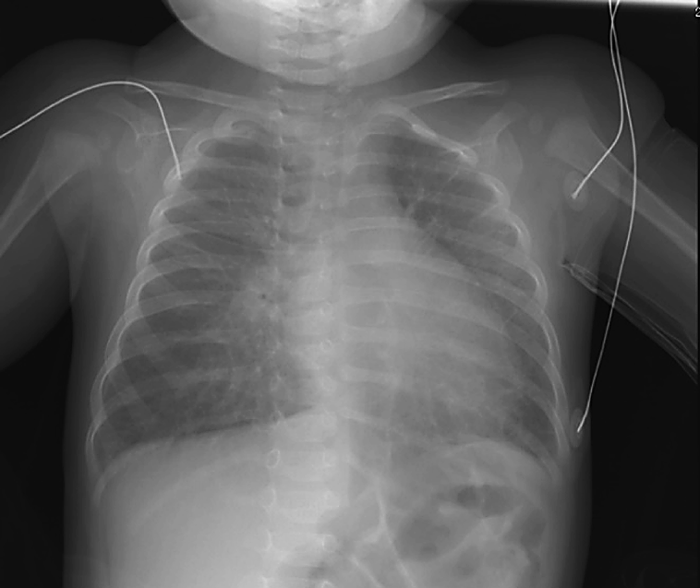

発熱前に弁破壊による急性僧帽弁閉鎖不全で発症した感染性心内膜炎の乳児例A Case of Infantile Infective Endocarditis Presenting Acute Mitral Regurgitation due to Valvular Destruction without Fever